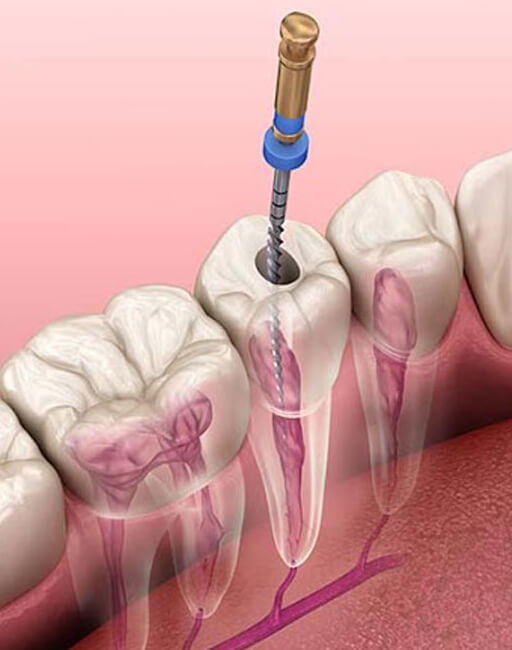

Overview of Endodontics